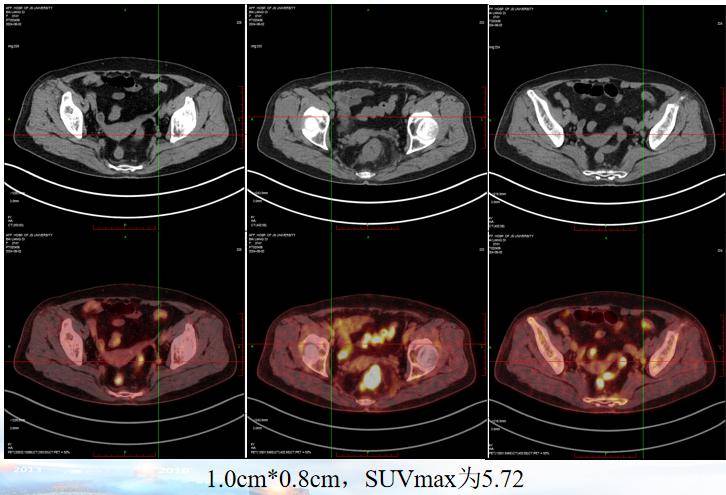

2024年8月2日行PET-CT检查:1、直肠壁不均匀增厚伴FDG代谢增高,符合直肠Ca表现。2、病灶周围及双侧盆壁小淋巴结伴FDG代谢增高,考虑转移。3、腹腔及腹膜后散在淋巴结,FDG代谢轻度增高,部分转移待排。

疗效评估:2024年10月30日复查CT及MRI,影像评估提示病灶较前明显缩小(肿瘤缩小43%,盆腔淋巴结退缩),疗效评估为部分缓解(PR)。